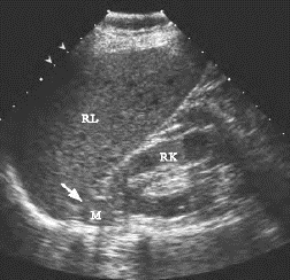

1.肾上腺皮质腺瘤超声表现(图28-3) 一侧肾上腺区见边界清晰的圆形或椭圆形的低回声区,其内部回声与肾实质回声强度相似,一般直径小于3cm。如该异常区位于右肾上腺区,还应观察其与下腔静脉间的关系,如两者紧邻,提示肿瘤较偏前部,如相距较远,则肿瘤位于肾上腺的偏外后部。

图28-3 肾上腺皮质腺瘤声像图

右侧肾上腺区低回声包块(M)